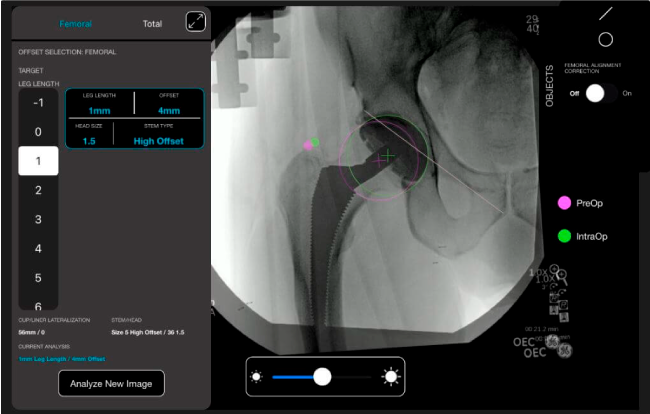

Desplazamiento y offset para posicionamiento óptimo del componente (vástago) femoral.

Con tecnología ONETRIAL® que calcula automáticamente el cambio en la longitud de la pierna y el desplazamiento para todas las combinaciones de implantes en una tabla fácil de leer.